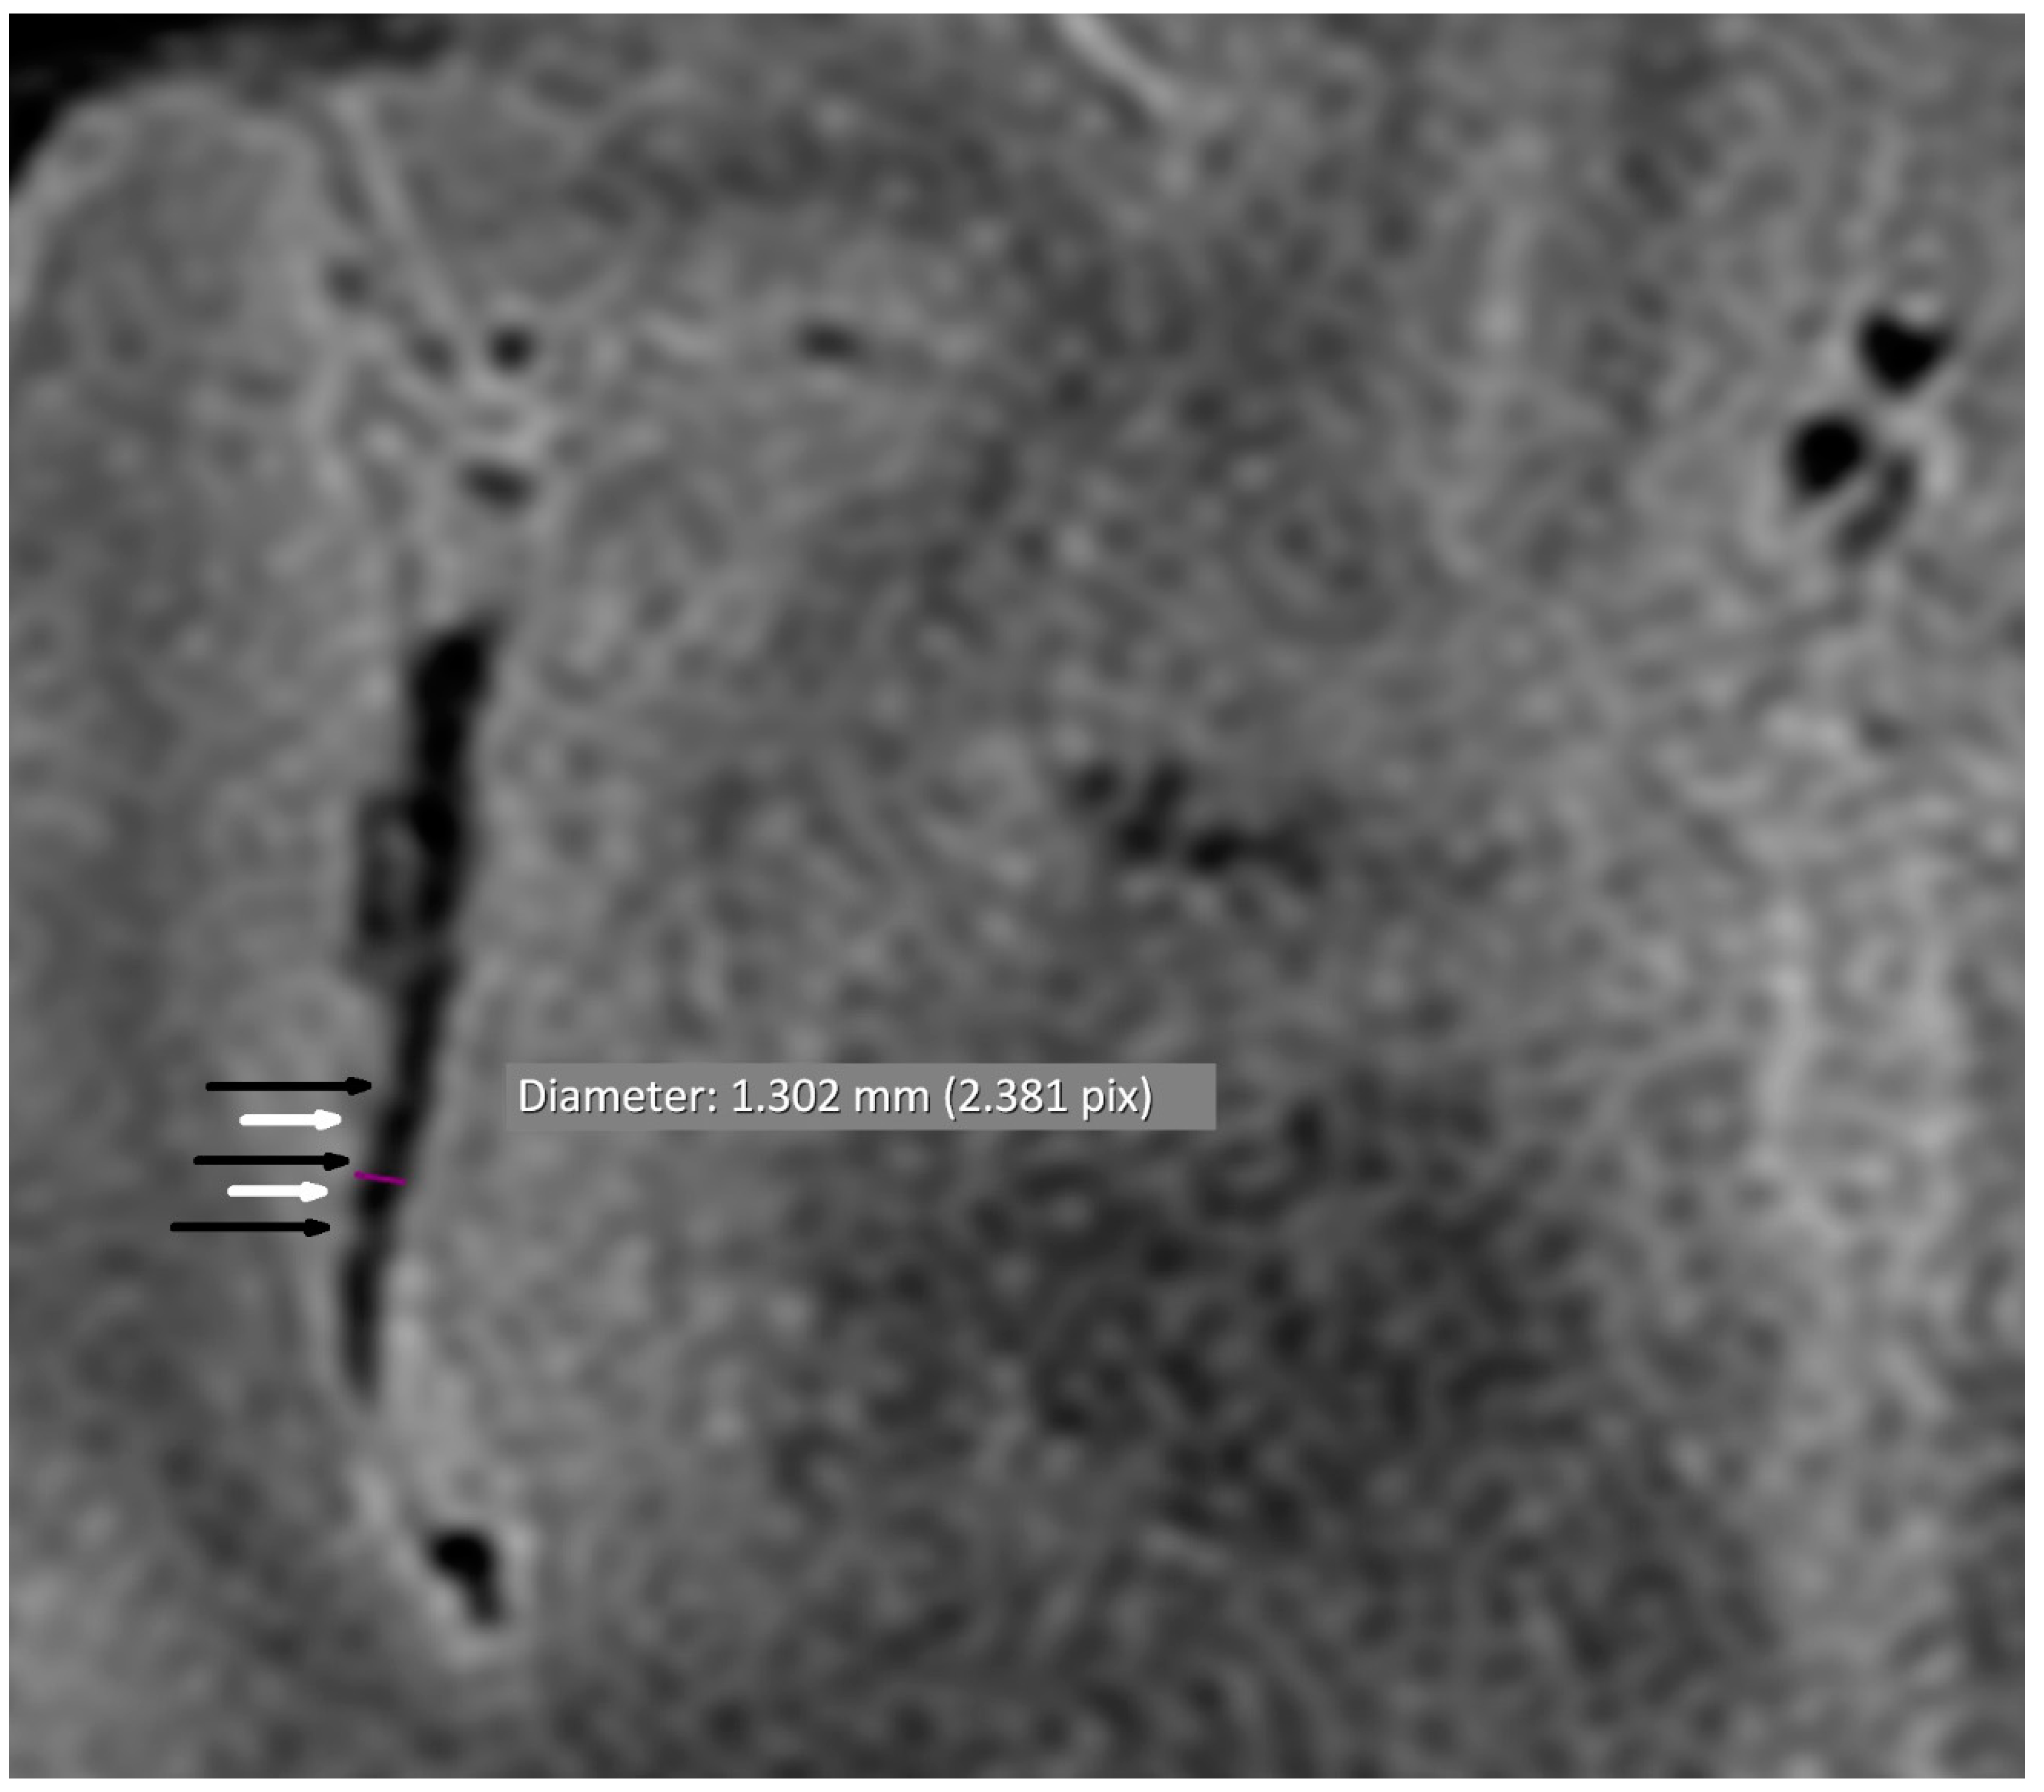

3.1. Vascular Alterations

| Alternating narrowing and dilatation in secondary vascular branches | 13/38 (34.2) | 1/38 (2.6) | <0.001 |

| Alternating narrowing and dilatation in tertiary vascular branches | 13/38 (34.2) | 1/38 (2.6) | <0.001 |

| Alternating narrowing and dilatation in secondary and tertiary vascular branches | 16/38 (42.1) | 2/38 (5.3) | <0.001 |